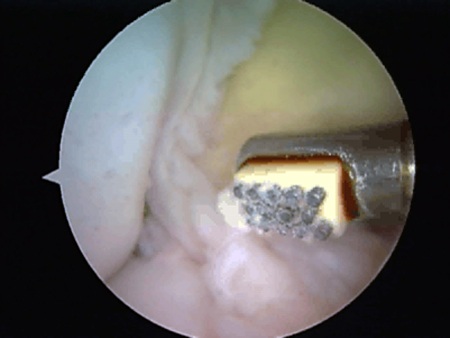

Từ khi có phương pháp phẫu thuật nội soi, là phương pháp hiện đại nhất đang được một số cơ sở y tế thuộc tuyến trung ương áp dụng, thì nhiều bệnh nhân đã tin tưởng để lựa chọn.

Bác sĩ Hoàng Công Anh cho biết: Ưu điểm của phương pháp này là ít gây đau, giúp phục hồi vận động sớm. Để tiến hành một ca phẫu thuật nôi soi khớp vai thì các phẫu thuật viên phải trải qua một thời gian khá dài để hoàn thiện dụng cụ và kỹ thuật khâu. Do đó, hiện nay, tại các tỉnh, nhiều cơ sở vẫn chưa ứng dụng kỹ thuật này.

Với ca mổ nội soi khớp vai lần đầu tiên tại Nghệ An, Bệnh viện ĐK115 tin tưởng rằng sẽ là địa chỉ tin cậy để các bệnh viện tuyến huyện , tuyến tỉnh và người bệnh lựa chọn. Đội ngũ các y, bác sĩ Khoa Chấn thương - Chỉnh hình Bệnh viện ĐK115 cũng xem đây là một kỹ thuật mới, cần được nâng cao hơn nữa về mặt kinh nghiệm và chất lượng phẫu thuật để đạt được các tiêu chí: an toàn, thành công.